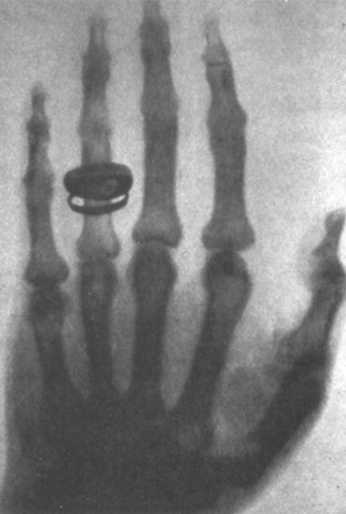

Первая радиография Рентгена, на которой мы видим руку его жены Берты.